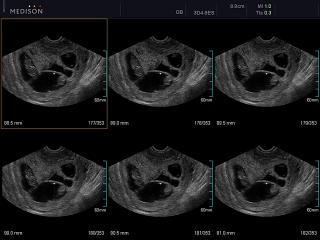

Atlas of ultrasound images - obsterics (pg. 5)

In the section "Оbsterics" of atlas the results of ultrasonic examinations of pregnant women with different durations of gestation are represented. Here you can see images of internally organs, cerebrum, cordis and the sex of the fetus, the sonograms of multiple pregnancy, the blood flow in placenta and umbilical cord, defects of fetal`s development, etc.